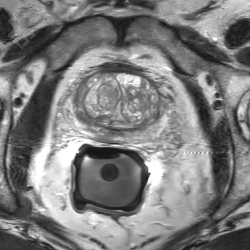

IRM Prostatique

La durée moyenne de l'examen est de 35 min. Dans le cas d'une injection, le manipulateur en radiologie vous administrera le produit de contraste. Vous entrendrez un bruit caractéristique à l'IRM faisant penser à un marteau piqueur. En début d'examen, pour limiter le péristaltisme, vous recevrez une injection d'un anti-spasmodique. Par ailleurs, l'introduction de la sonde rectale pourra être désagréable, mais pas douloureuse.